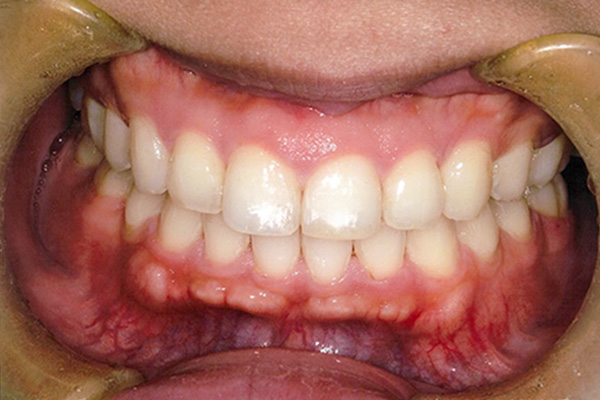

| 症状 | 下顎第一大臼歯の欠損 |

| 想定されるデメリット | 臼歯の近心移動が非常に難しい。高度なテクニックが必要である。 3D-LST矯正治療法を用い、抜歯を最小限に抑えながら歯の近心移動を実施。 |